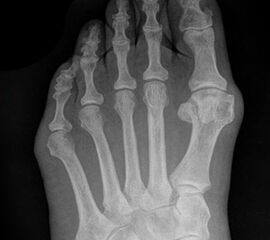

Abb. 7 a, b: Typ II Deformität mit prä- (a) und postoperativem Röntgenbild (b) mit K-Draht Osteosynthese und gleichzeitiger Hallux valgus Korrektur.